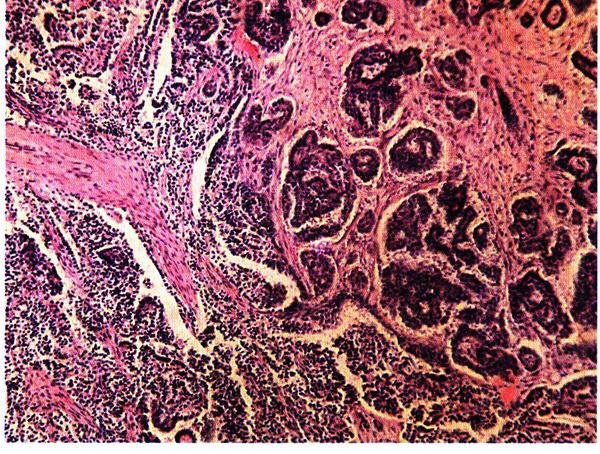

Удельная частота первичного рака составляет не более 5%. При первичном раке опухоль формируется из покровного эпителия яичника, следовательно, в ней отсутствует смешение доброкачественных и злокачественных элементов. Первичным раком называют злокачественные опухоли, первично поражающие яичник. По гистологическому строению первичный рак яичников – это злокачественная эпителиальная опухоль железистого или папиллярного строения (рис. 16.19).

Рис. 16.19. Серозный папиллярный рак яичника (серозная цистаденокарцинома). Окраска гематоксилином и эозином, х 200. Фото О.В. Зайратьянца